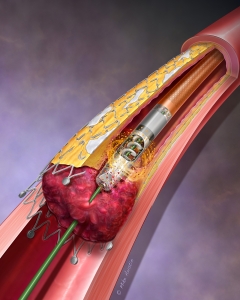

Internal Art Medical Illustration

Blending Art, Anatomy and Science for Creative Visuals

Patient & Professional Marketing

Welcome to my Patient and Professional Marketing page, where I harness the power of anatomical illustrations to educate and empower both patients and medical professionals. My unique approach combines artistry and education to convey complex surgical procedures and the utilization of medical devices in an easily understandable manner.